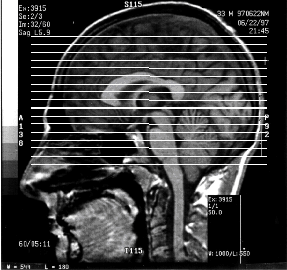

Anatomical Views

• Mid-Sagittal View of Nestor's Brain ,

...sliced "right between the eyes".